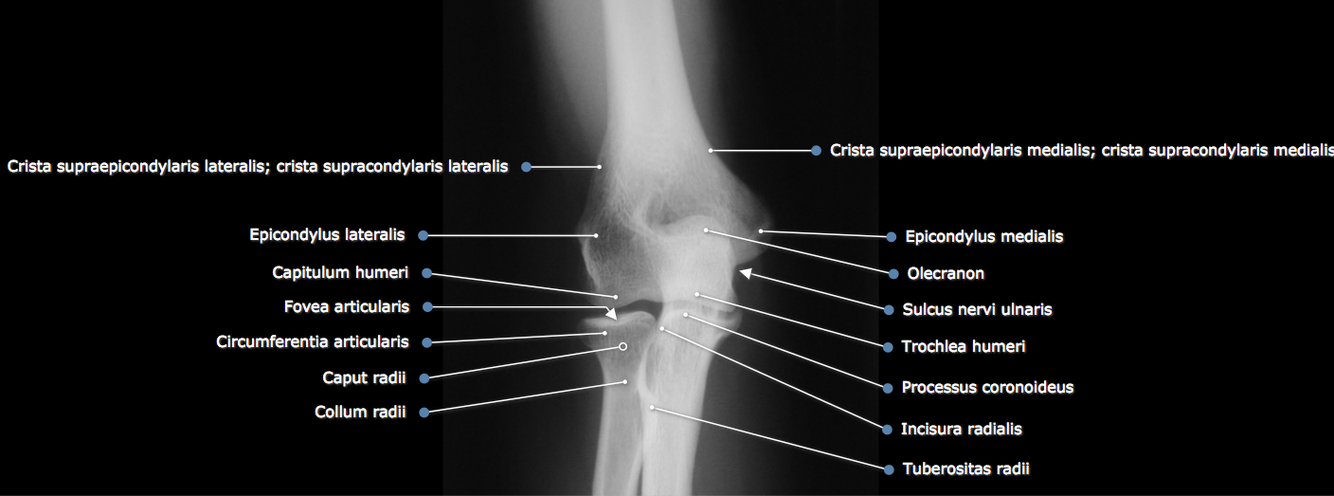

Hvilke strukturer er mest utsatt ved en distal humerusfraktur?

N.radialis og a.brachialis

Hvilke strukturer er man redd for ved reponering av en luksert albue?

Fraktur i processus coronoideus, caput/collum radii eller capitellum humeri.